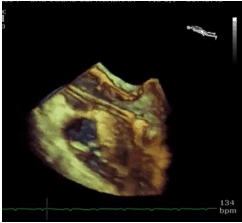

Em relação à figura a seguir, identifique a condição patológica evidenciada no fluxo aórtico na via de saída do VE.